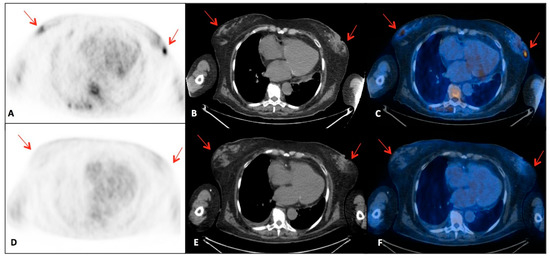

2. Case Presentation